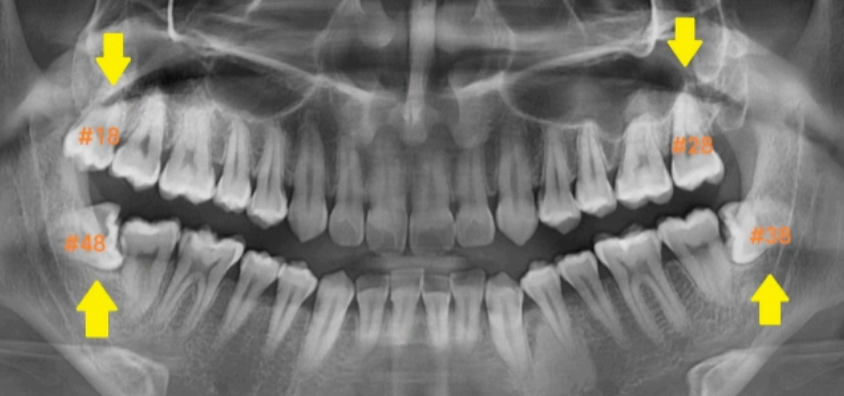

사진 속 4개의 사랑니가 있는데요.

한눈에 보기에도 아래쪽에 위치한 사랑니는

누워있죠~?

누워있고 숨어있는 사랑니는

발치 난이도가 증가하지만

예쁘게 잇몸 밖으로 올라온 사랑니,

윗니 사랑니는 수월하게 뽑을 수 있습니다 .

이렇게 누워서 난 사랑니는

수직으로 뽑을 수가 없기 때문에

쪼개서 뽑아야합니다.

발치 난이도도 올라가고

뼈도 삭제해야해서

발치 후 통증이 심할 수 있습니다.

해부학적으로 하치조 신경관과 근접하기 때문에

뽑고 나서 신경 손상 가능성도 있고요

위에 사랑니는 아래뼈에 비하여

뼈도 약하고

똑바로 나온 경우가 많아서

발치 난이도가 쉬운편입니다.